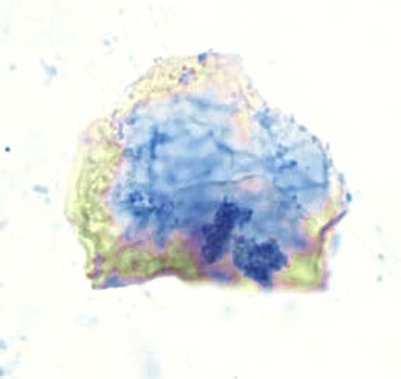

La coloration Papanicolaou est la coloration de référence utilisée en médecine pour différencier les cellules en fonction de leur maturité et de leur activité métabolique.

The Papanicolaou staining is the reference staining used in medicine to differentiate cells based on their maturity and metabolic activity.